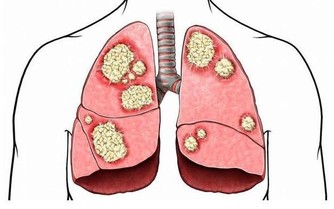

●光在足底就有136個穴位反射區,分別對應人體的五臟六腑,這個理論比較複雜。簡單說來,你要知道:經常雙腳互打,相當於在調理全身五臟六腑。

中醫認為,腳與人體的五臟六腑、四肢百骸都有極為密切的關聯。

寒從腳下起,病從腳底除!腳底的反射區映射全身!每天睡前10分鐘,雙腳互打幾分鐘,相當於給全身吃補藥!